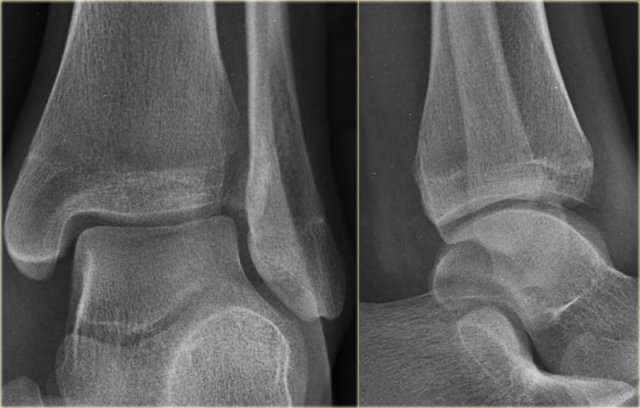

Here another example.

There is only a small metaphyseal fragment, which is usually the case (red arrow).

The fracture through the epiphysis is indicated by the blue arrow.